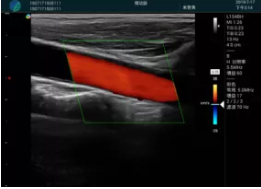

可視化甲狀腺穿刺引導

頸動脈血流充盈飽滿,無外溢

肝內(nèi)血管顯示清晰,血流敏感無外溢

病例二:

甲狀腺囊性結(jié)節(jié),囊壁鈣化,透聲好

甲狀腺囊性占位

2001年美國健康護理研究和質(zhì)量監(jiān)督局(AHRQ)批準了一項關于提高患者安全性的報告,建議:在頸內(nèi)靜脈中心置管術(shù)時使用超聲引導。此后超聲引導穿刺被用于幾乎所有的急診穿刺操作,尤其是血管穿刺。